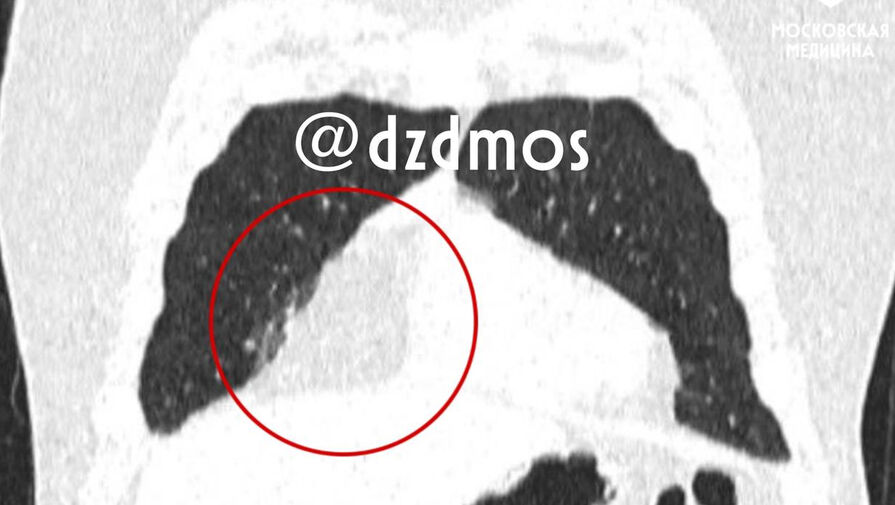

Мальчик жаловался на боли в груди и одышку, поэтому родители отвели его в поликлинику, где на рентгене грудной клетки медики нашли признаки опухоли. Компьютерная томография подтвердила наличие жировой опухоли размером 17 на 6 сантиметров. Для дальнейшего лечения пациента направили в больницу Сперанского.

«Наш пациент страдал ожирением II степени. В его случае новообразование срослось с перикардом (сердечной сумкой) и диафрагмой, сместило сердце влево и еще поджимало правое легкое, поэтому мальчик чувствовал себя плохо», — рассказал детский хирург высшей категории Владимир Гацуцын.